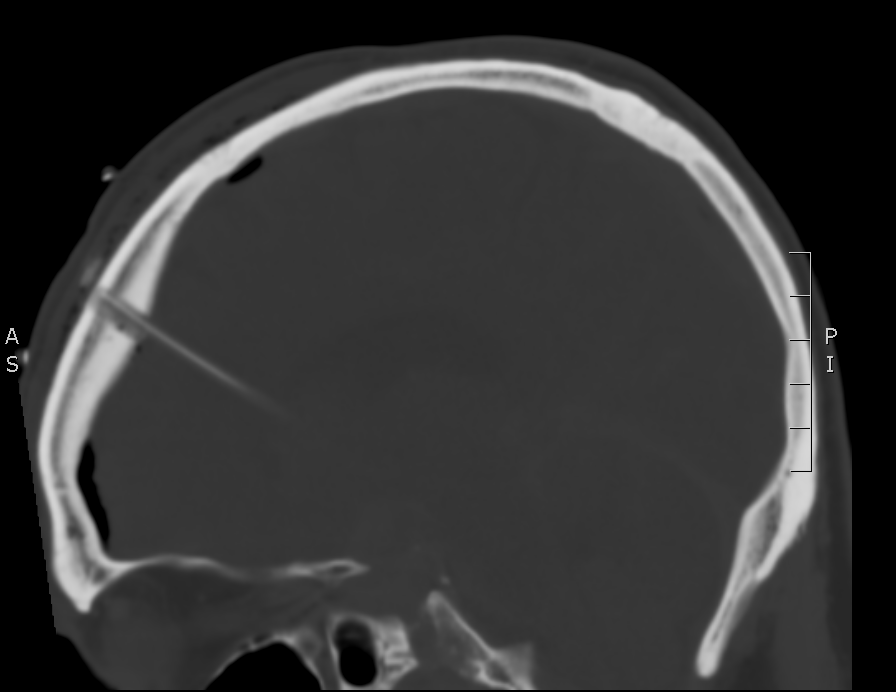

There is a lot going on in this CT – but you may have realized that there is diffuse subarachnoid hemorrhage. There are a number of other findings that we’ll walk through. First, take a look at using our coronal and sagittal views – fun fact, these are simply computer reformats of the axial above.

Sagittal CT

- Yellow Arrow – a tricky one, this is a ventricular drain, or EVD – commonly used to prevent the development of hydrocephalus after subarachnoid hemorrhage. Look for it again in the coronal and sagittal images above.

If you go back to the coronal and sagittal images you can try to find the same structures. You’ll also see that there is a fair amount of subarachnoid hemorrhage anterior to the brain stem.